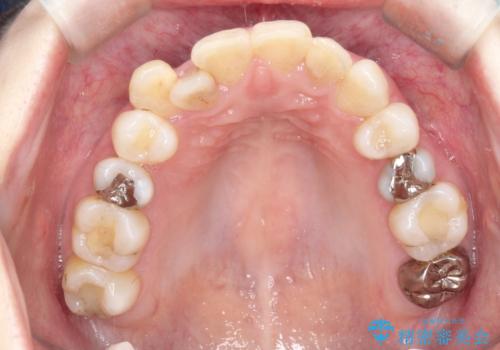

初診時の歯並びの状態としては、上下ともに前歯部中心としたの中等度のがたつき(叢生)があり、全特に左上の前歯は1本だけ引っ込んでおり、犬歯は外に飛び出した状態でした。

抜歯は行わず上顎の奥のスペースを利用して歯をスライドする方法の他に歯列弓の拡大やディスキング(歯と歯の間の隙間を作る処置)を行い叢生を改善しましています。

歯の大きさの不揃いが原因の正中のズレは、ディスキング量を調整することで合わせました。